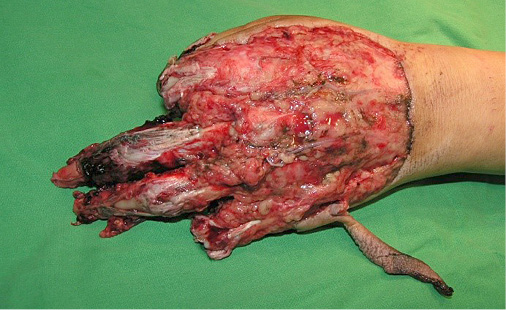

1 pav.

2 pav.

Kairės plaštakos minkštųjų audinių Degloving amputacija. Nugarinis ir delninis paviršiai (1 ir 2 pav.)